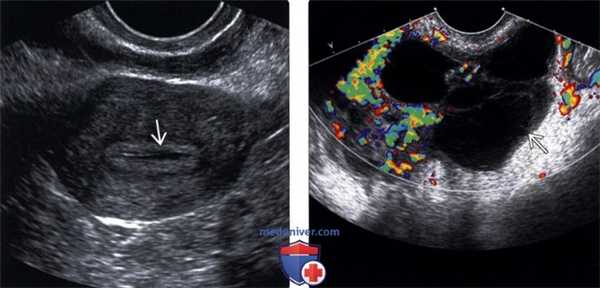

(Слева) Трансвагинальная ультрасонография матки в коронарной плоскости у пациентки с воспалительными заболеваниями органов малого таза (ВЗОМТ); определяется жидкость эндометрия, что указывает на эндометрит.

(Справа) Трансвагинальная цветовая допплерография в коронарной плоскости: многокамерный тубоовариальный абсцесс с детритом и окружающей гиперемией.